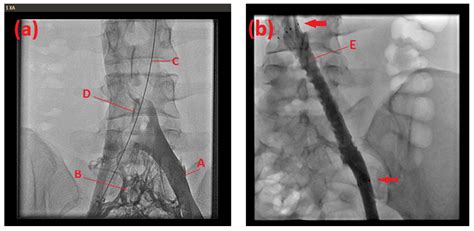

May-Thurner Syndrome, also known as iliac vein compression syndrome, occurs when the left common iliac vein is compressed by the right common iliac artery against the spine. This compression creates a mechanical obstruction that slows down blood flow from the left leg back toward the heart. When blood flow is restricted, the blood is more likely to pool and clot, a condition known as Deep Vein Thrombosis (DVT). If left untreated, these clots can potentially break loose and travel to the lungs, resulting in a pulmonary embolism, which is why early detection is critical.

The good news for those diagnosed with MTS is that the outlook for Maythurner Syndrome life expectancy is excellent, provided the patient adheres to a structured treatment plan. Medical advancements in endovascular surgery have made it possible to treat the compression effectively with minimal invasiveness. The standard approach typically involves angioplasty and stenting. By placing a stent in the compressed vein, physicians can permanently open the vessel, restoring normal blood flow and significantly reducing the risk of future blood clots.

One of the most important factors in maintaining a normal Maythurner Syndrome life expectancy is regular monitoring by a vascular surgeon or interventional radiologist. Periodic ultrasound imaging (Duplex scans) allows doctors to ensure that the stent remains patent—meaning it is open and functioning correctly—and that there is no narrowing or obstruction developing within or around the stented area. Through proactive follow-up, any minor issues can be addressed before they escalate into serious health concerns.